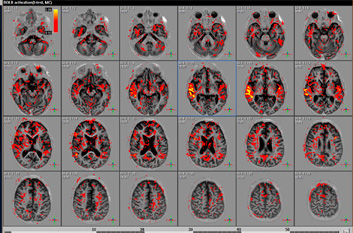

Цель: Разработка и внедрение в клиническую практику исследований сохранности проводящих путей (DTI) и основных функций мозга (fMRI) после травмы и после периода реабилитации. Описание проекта: Методика функционального МРТ [1, 2] основана на визуализации изменения кровоснабжения при функциональной активности мозга - при этом увеличивается потребление клетками кислорода, что приводит к росту концентрации окисленного гемоглобина и, как следствие, к изменениям интенсивности МРТ сигнала в зоне активации (BOLD-эффект) [3-5]. При тяжелой травме мозга фМРТ позволяет оценить сохранность основных функций мозга (движение, зрение, речь, когнитивные функции). Таким образом, необходима разработка и клиническая апробация комплекса структурных и функциональных исследований, в том числе для пациентов в бессознательном состоянии (с использованием пассивной активации). Результаты: Разработанный комплекс исследований позволяет оценить региональную активность мозга при выполнении заданий и в состоянии покоя, оценить вторичные посттравматические изменения в веществе мозга.

Результаты исследования пациента в коме: при прослушивании сказки наблюдаются паттерны активации слуховой зоны.